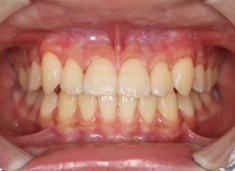

検査時のレントゲン分析では、上下顎の関係は、上顎の劣成長があり下顎前突傾向という値がでておりましたが、前歯ジャンプ後はフェイスマスクの効果もあり、上下顎の関係は正常化しています。

上顎が若干優位になっていますので、今後の下顎の成長のための貯金になっているくらいです。